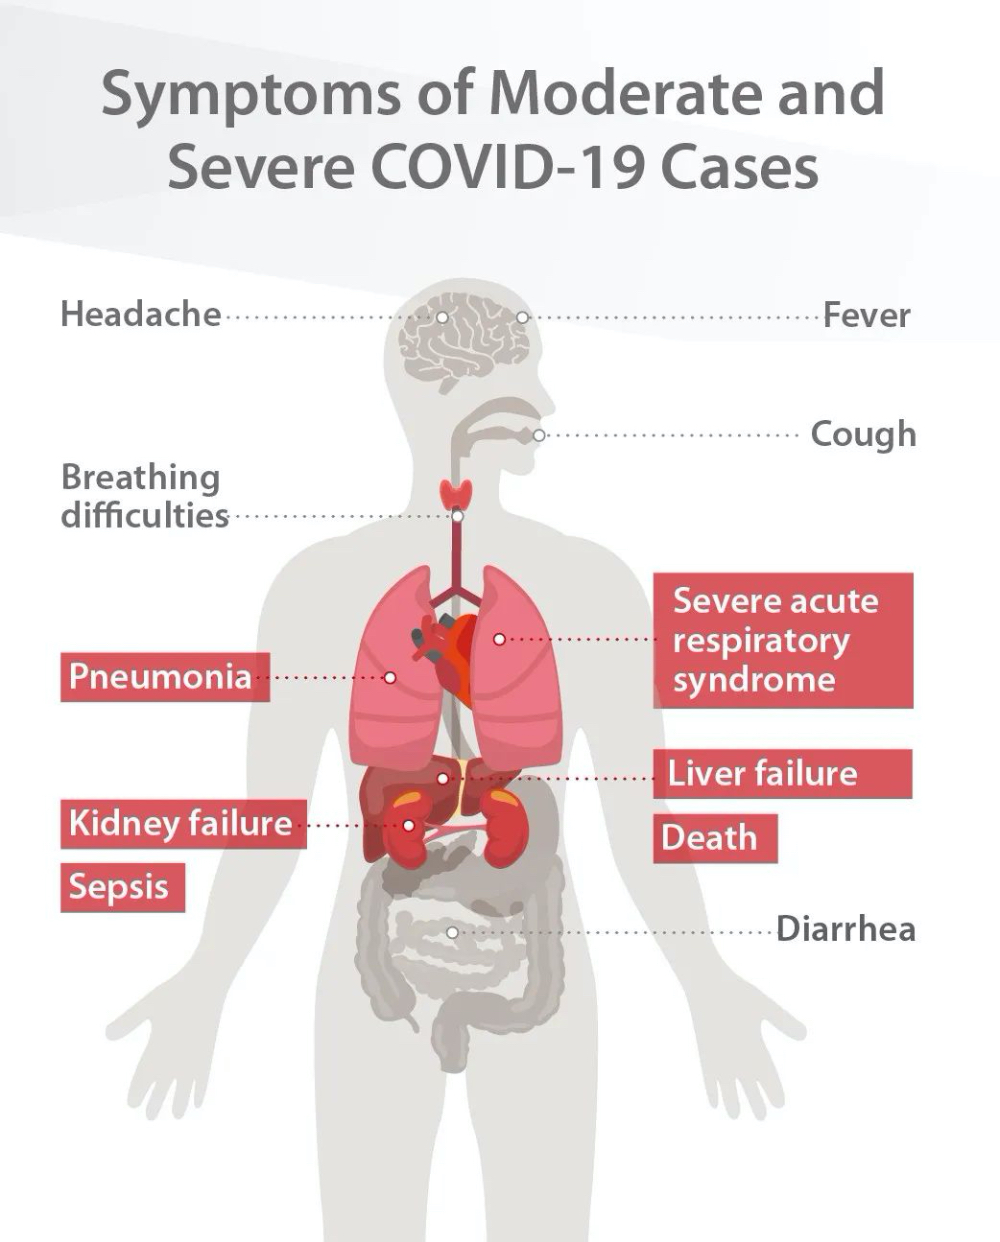

Though most confirmed coronavirus cases are moderate, there can be rapid deterioration for severe patients who will suffer respiratory failure, septic shock or multiple organ dysfunction, threating life. WHO officials estimate that the global death rate for COVID-19 cases stands at around 3.4%. [1] Early identification of indicators distinguishing severe patients from moderate ones can facilitate faster medical interventions such as intensive care for the critically ill, thus lowering the mortality rate and optimizing use of the extremely strained medical recourses.

A. From the comparison between CBC tests from moderate and severe cases, it could be concluded that, as the patientвАЩs condition deteriorates, his or her: